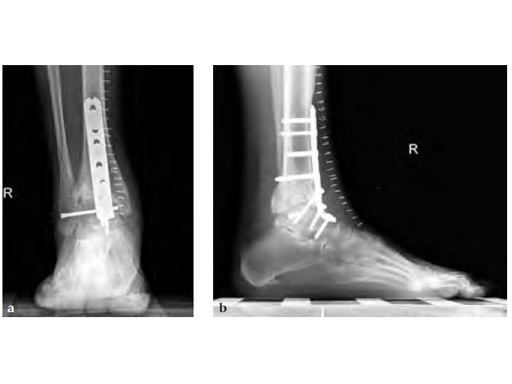

Anterior approach through the same anterior incision with placement of anterior plate. Orthogonal screw was added for stability through the fibula into the talar body. Preserving fibula makes it easier for future reconstruction should that be possible (ie, placement of implant in the face of previous infection currently not recommended).